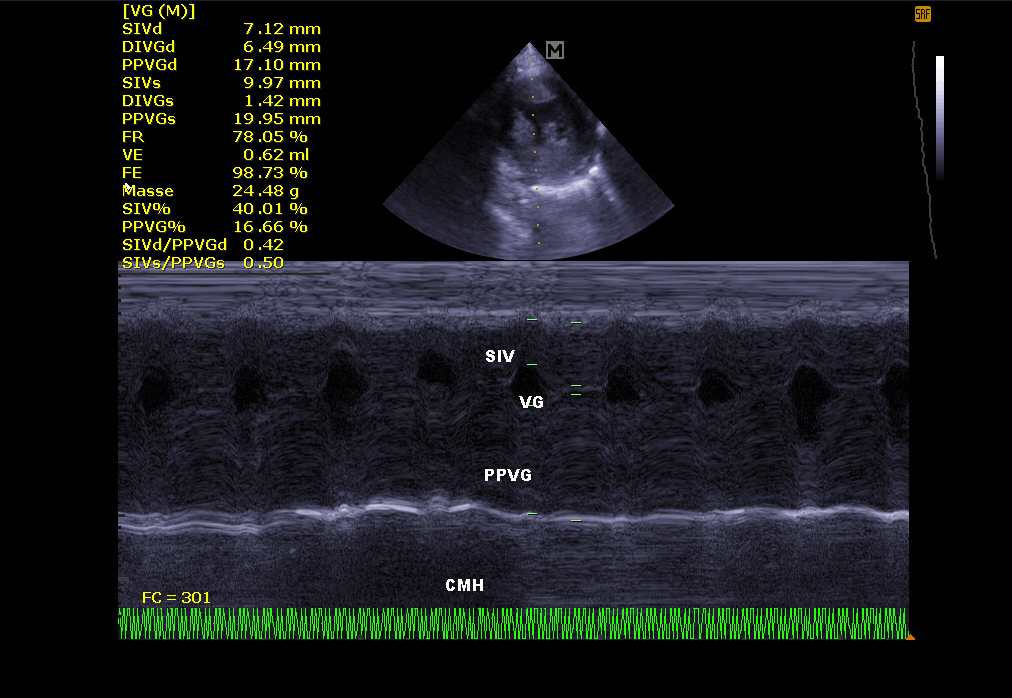

Echokardiographie:

Es ermöglicht die Visualisierung der verschiedenen Teile des Herzens (Wände, Hohlräume, Klappen) und die Identifizierung von Anomalien, die eine korrekte Herzfunktion verhindern. Bei Herzinsuffizienz ermöglicht die Echokardiographie auch eine regelmäßige Überwachung der Herzmorphologie. Es ist dann einfacher, die Behandlung an Ort und Stelle neu einzustellen.